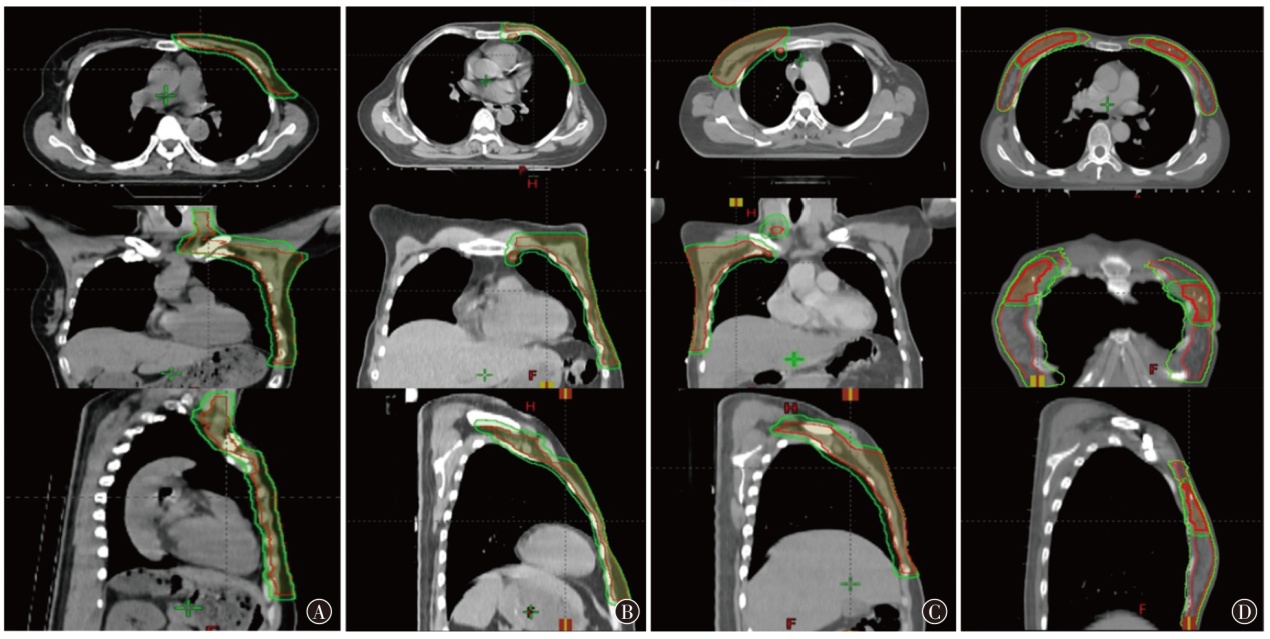

目的探索质子放疗和光子放疗应用于乳腺癌治疗的剂量学特点。方法选取2024年1月至2024年5月在山东省肿瘤防治研究院(山东省肿瘤医院)需行放疗的4例女性乳腺癌患者为研究对象,靶区范围分别为左侧胸壁加左侧锁骨上下淋巴引流区、左侧胸壁加左侧内乳、锁骨上下淋巴引流区、右侧胸壁加右侧内乳、锁骨上下淋巴引流区和双乳腺并瘤床加量。根据靶区处方剂量和危及器官限量要求,分别设计质子调强放疗(IMPT)、光子固定野调强放疗(IMRT)(双侧乳腺为螺旋断层放疗)计划。评估各计划靶区的适形指数(CI)、均匀性指数(HI)、梯度指数(GI)及危及器官受量,对比IMPT和光子放疗的剂量学特点。结果4例乳腺癌患者的IMPT和光子放疗计划均能满足临床要求,其中IMPT计划HI值(0.10~0.14)与光子放疗计划(0.10~0.12)相当,光子放疗计划的平均CI较IMPT计划高0.10,平均GI较IMPT计划低0.55。IMPT计划的患侧肺和心脏的Dmean更低,特别在低剂量区域(V0-3)显著少于光子放疗计划;患侧肺的Dmean分别降低了12.2%、6.1%、16.1%和34.8%,心脏的Dmean分别降低了47.2%、57.0%、72.4%和83.0%。IMPT计划的患侧肺V20并不比光子放疗计划更低(单侧乳腺:IMPT为30.0%~34.0%,IMRT为29.0%~35.9%)。结论IMPT在保证乳腺癌靶区覆盖的情况下显著降低了患侧肺和心脏的Dmean,使更多区域不受照射、保护周边更多的正常组织。但是在患侧肺的V20方面,IMPT并未表现出比光子放疗计划更有优势。

| 1 | 左侧 | 53 | 左侧胸壁加左侧锁骨上下淋巴引流区 | IMRT:50 Gy/25 f;IMPT:50 Gy(RBE)/25 f |

| 2 | 左侧 | 60 | 左侧胸壁加左侧内乳、锁骨上下淋巴引流区 | IMRT:50 Gy/25 f;IMPT:50 Gy(RBE)/25 f |

| 3 | 右侧 | 48 | 右侧胸壁加右侧内乳、锁骨上下淋巴引流区 | IMRT:50 Gy/25 f;IMPT:50 Gy(RBE)/25 f |

| 4 | 双侧 | 44 | 双侧乳腺并瘤床加量 |

TOMO:乳腺50.4 Gy/28 f、瘤床64.4 Gy/28 f;IMPT: 乳腺50.4 Gy(RBE)/28 f、瘤床64.4 Gy(RBE)/28 f |